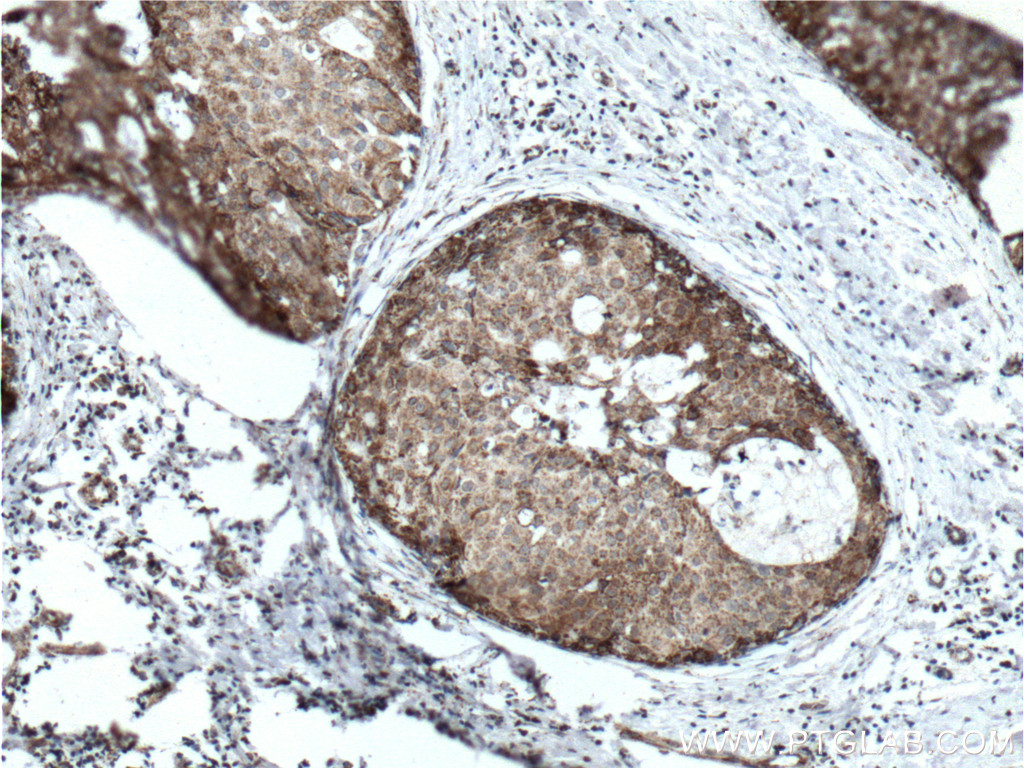

| Positive IHC detected in | human breast cancer tissue, human heart tissue Note: suggested antigen retrieval with TE buffer pH 9.0; (*) Alternatively, antigen retrieval may be performed with citrate buffer pH 6.0 |

| Immunohistochemistry (IHC) | IHC : 1:50-1:500 |